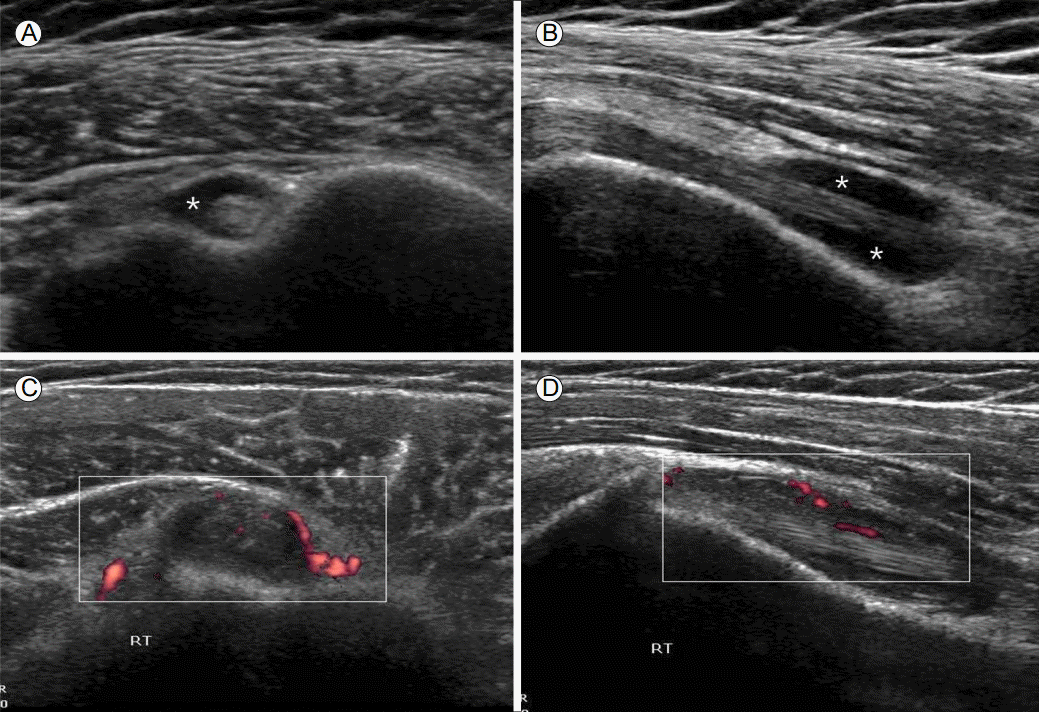

- 석회성 건염

- 어깨 힘줄에 칼슘이 침착되어 염증과 통증을 유발하는 질환입니다.

- 특별한 외상 없이도 갑자기 매우 심한 통증이 나타날 수 있으며, 젊은 층에서도 발생할 수 있습니다.

- 주사와 약물치료로 통증을 완화할 수 있습니다.

- 밤에 통증이 심해지며, 팔을 들어 올리지 못할 정도로 통증이 발생할 수 있습니다.

- 석회가 힘줄에 축적되는 과정에서 극심한 통증이 나타나기도 합니다.